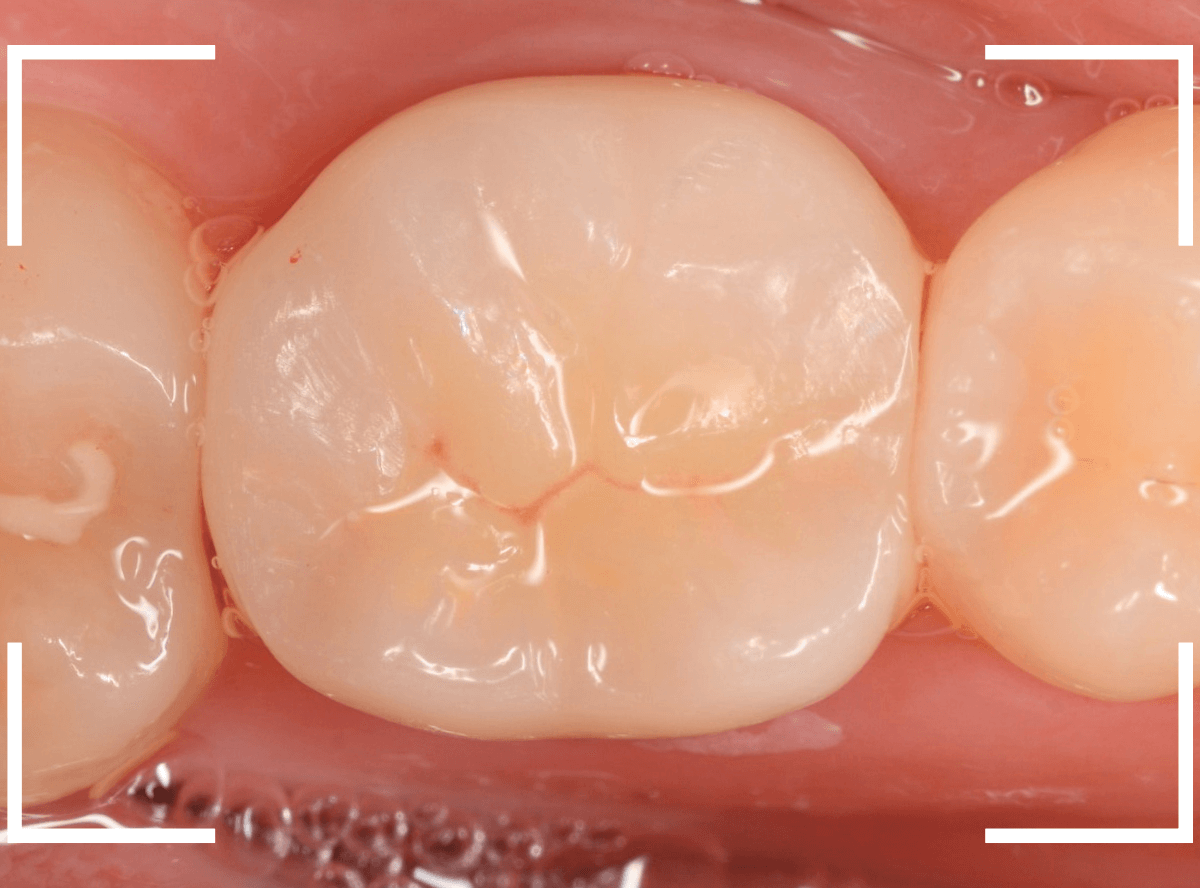

お口の中にsetしたところです。

周りの歯と自然に合わせられたかと思います。

お口の中全体でみたところです。

全体で見ても、違和感少なく仕上げられたかと思います。